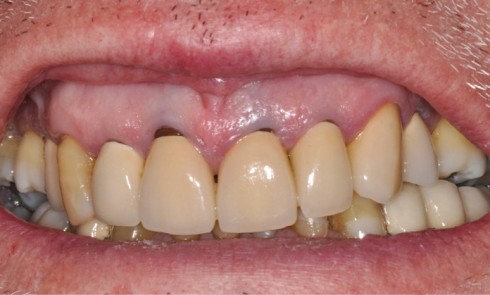

Article réservé à nos abonnés Harmonisation des collets avec allongement de couronnes cliniques

L’esthétique du sourire impose la recherche d’un équilibre entre le parodonte et les dents, d’une harmonie entre le rose et...